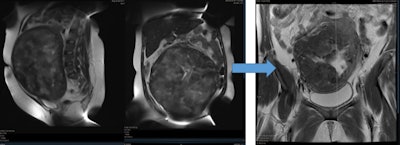

خلال عملية معالجة الورم الليفي الرحمي بالقثطرة.

تتميز معالجة الأورام الليفية الرحمية عن طريق القثطرة بأنها أبسط و بأن نسبة المشاكل والاختلاطات أقل مقارنة بالاستئصال الجراحي حيث يتم اجراء القسطرة بدون تخدير عام و ياخذ الاجراء 45 دقيقة و تخرج المريضة من المشفى في نفس اليوم.

تبعاً لما يعتقد بأنها اكبر دراسة الأولى في الشرق الأوسط فإن معالجة الأورام الليفية عن طريق القثطرة تتم عبر قطع التروية الدموية للأورام الليفية المسببة للاعراض وتتمتع بنسب متقاربة مع الجراحة من ناحية الأنجاب للنساء اللواتي يرغبن بالحمل.